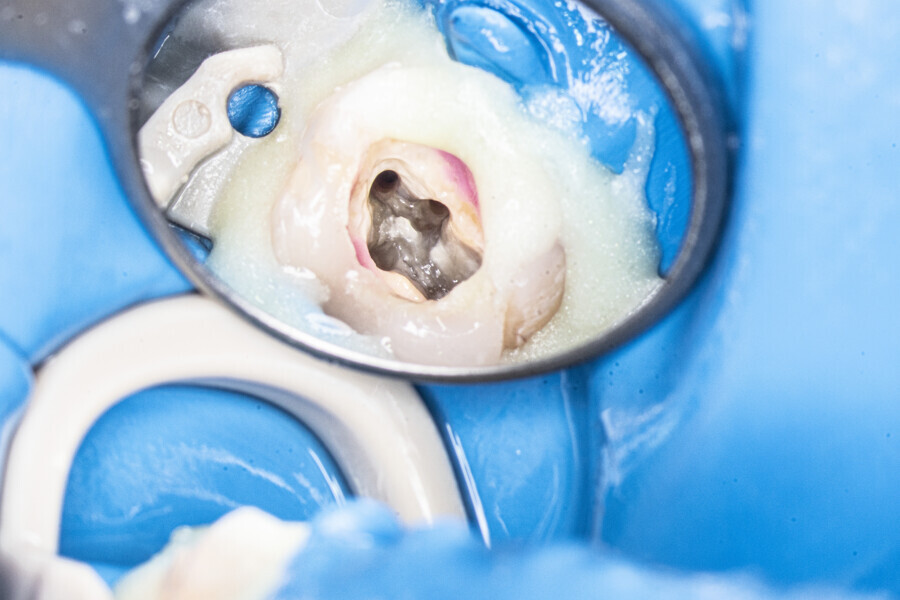

Case 2 (Figs. 27–36)

A 25-year-old female patient presented to the office owing to constant pain related to the mandibular left first molar. Pulp necrosis was diagnosed. After the emergency appointment, the patient was referred for complete treatment. The tooth was treated in the same manner as described in the previous paragraphs. After creation of the access cavity, the orifices were located. In the root chamber, the orifices of the MB, mesiolingual, DB, distomesial and distolingual canals were present. After pre-flaring and preparation of the middle third, the LPE enhanced irrigation protocol with the SkyPulse laser was performed. After the irrigation protocol in the mesial root, the irrigants started to flow between lingual and buccal canals. Such an observation suggested to the operator that some space in the isthmus had been created. It is worth mentioning that at this stage apical enlargement was not performed. Final preparation of all five canals was performed with the reciprocating file, and the final irrigation protocol was performed as in the previous case. The radiograph clearly revealed that the isthmus space was filled with the sealer. The radiograph and CBCT image revealed that there were four portals of exit in the mesial root.